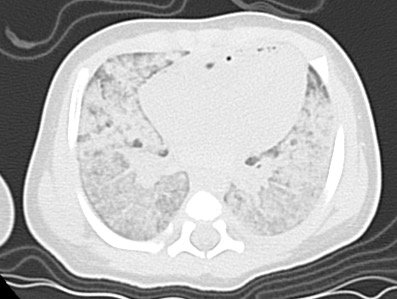

• 気管・気管支内には水濃度のものが充満している。固形異物と思われるものは気道に認めない。両側肺の背側肺はスリガラス状の濃度上昇に気管支血管束周囲の間質拡大が加わった状態。腹側の肺は上葉では気管支血管束周囲の間質拡大が加わった形となり、中葉や舌区では含気が残った形となっている。気胸、間質性肺気腫など空気漏出は指摘できない。胸水は認められない。

• 両側肺は生前の肺炎・誤嚥また窒息などの可能性を否定できないが、死戦期の急性左心不全の像としても理解できると思われる。